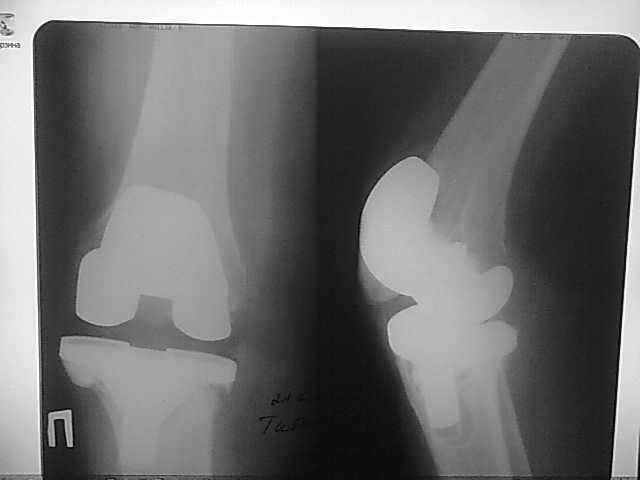

2006, в одной клинике установлен эндопротез правого коленного сустава, через год

нестабильность обоих компонентов, доктор выполняет ревизию обычным протезом с задним

стабилизатором. В октябре 2008 - нестабильность, свищ. В другом стационаре все удалено,

Имя     : 2-26.09.07.jpg

Тип     : image/jpeg

Размер  : 14550 байтов

Описание: отсутствует

Url     : http://weborto.net:8080/pipermail/ortho/attachments/20090219/242fe889/attachment-0007.jpg